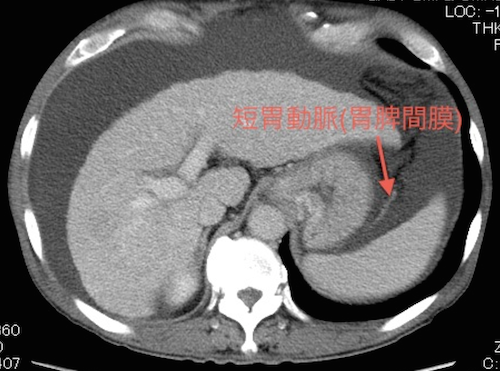

| 胃脾間膜 | 短胃動静脈 |

短胃動脈は胃脾間膜のメルクマールとなります。